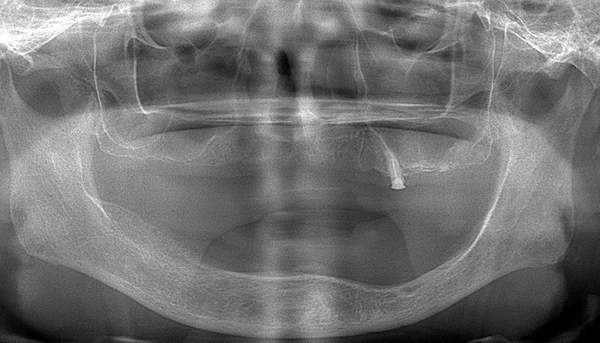

3.レントゲン診査

レントゲンで、顎の骨の厚みや、顎の関節の状態と位置を見ていきます。また、噛む力は強いのかなども診ることができます。 歯があれば、その状態も診査していきます。

上下の入れ歯が外れやすくなったということでいらっしゃいました。 顎の骨はしっかりしていましたので、精密な型取りさえすればしっかりした入れ歯がつくれると思いました。 また下には6本歯が残っていましたが、虫歯になっている歯もありました。 かぶせ物のなかで大きな虫歯があった歯があり、1本だけ残せない状態でした。

治療内容 レントゲンをみて最低限の長さのインプラントを右上の奥歯の位置に埋入しました。インプラントと骨の結合(オッセオインテグレーション)と歯肉の治癒を待ち、アバットメントをいれて型取りをして、入れ歯を作成しました。極力薄くするために、金属をもちいた入れ歯にしました。